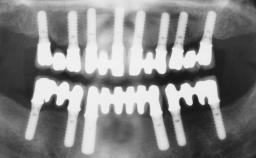

A 31-year-old man presented to our clinic 30 days after a motor vehicle accident in which he had suffered a dentoalveolar fracture in the anterior maxilla, including avulsion of teeth 12 and 11 and luxation of tooth 21. He was first treated on the night of the accident in a small city hospital with no oral and maxillofacial surgeon on the staff. A wired retention had been applied and the teeth repositioned to the best of the clinicians’ abilities. When he first presented to our care, the patient showed extrusion of teeth 12 and 11 associated with gingival recession due to bone loss in the anterior maxilla, and the stainless steel wires were still present.

# of Implants 3

Type of Implants One-Piece|Reduced-Diameter

Bone Augmentation Horizontal|Staged|Vertical

Augmentation Materials Autogenous chips|Autogenous block(s)